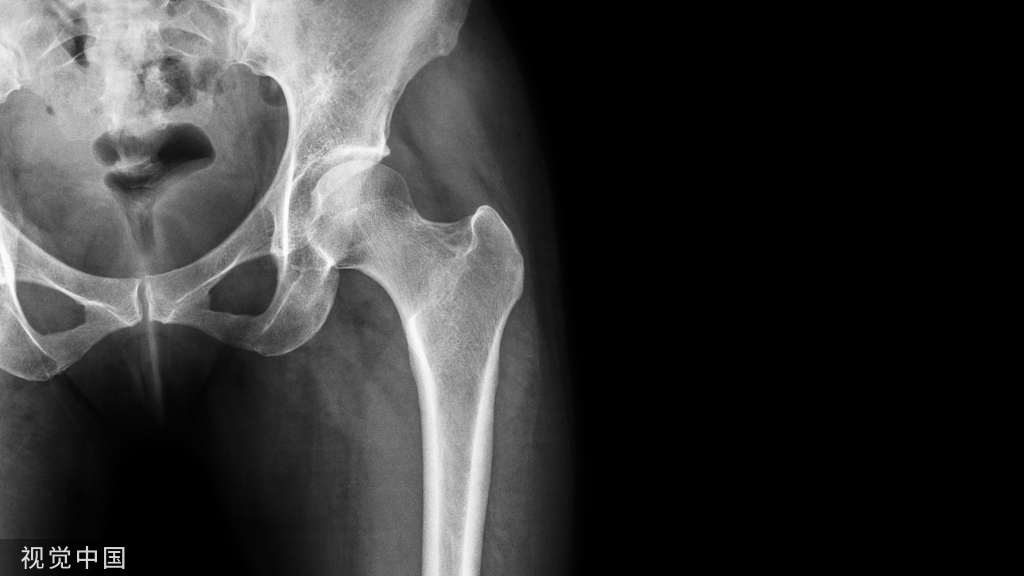

最后透视: